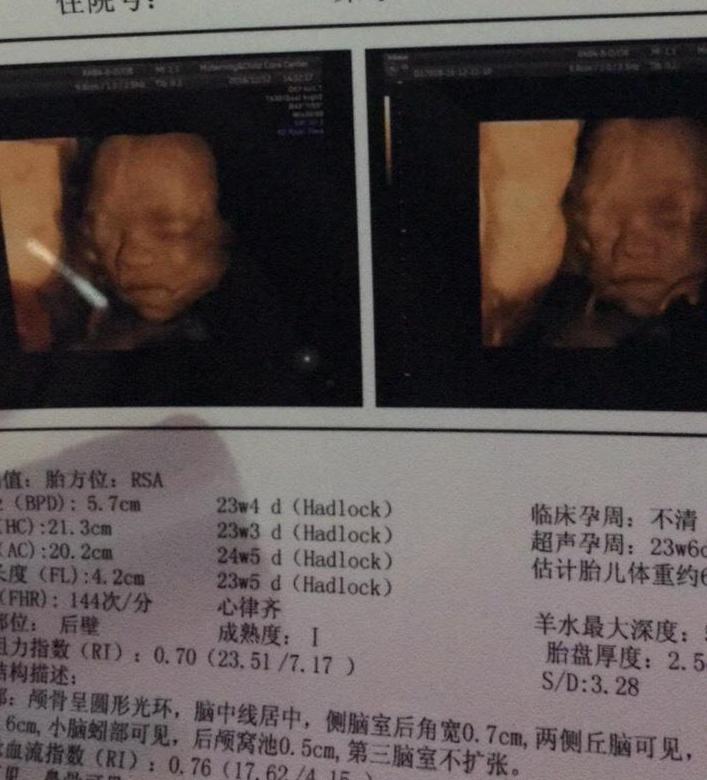

前3个月就已经预约了今天8点做四维,所以一大早就和老公7点就到了医院,然后开始走楼梯,走了上下楼梯一共5趟,而且使劲的和宝宝讲话,到了8点整就听见医生叫我进去,我是第一个做,好激动。看着医生用仪器在我肚子扫了扫就看见了宝宝的样子,太神奇了。还好之前听了很多宝妈们意见,在做四维前爬楼梯就能更快照号四维,大概花了半个钟就搞定了,医生说宝宝很健康就让我出去等报告。

拿到报告的一瞬间就赶紧去了找医生,让医生看,医生说宝宝很健康而且发育很好,没什么问题,搞定这次检查就不用再检查了,在家平时记得数学数胎动,留意宝宝的动向,有不对劲的要马上来医院检查,其余到32周再来复查就可以了。之后老公就拿着我的报告找了一些会看数据的熟人帮忙看了下是男娃还是女娃,但是熟人不愿意表面说,只是说恭喜有后了,我们一头雾水的,最后回家想了想,再根据我有很多症状都偏向男娃,估计是跟我们说是个儿子吧,哈哈。不过还是要生下后才晓得准不准,希望不翻盘就好了。